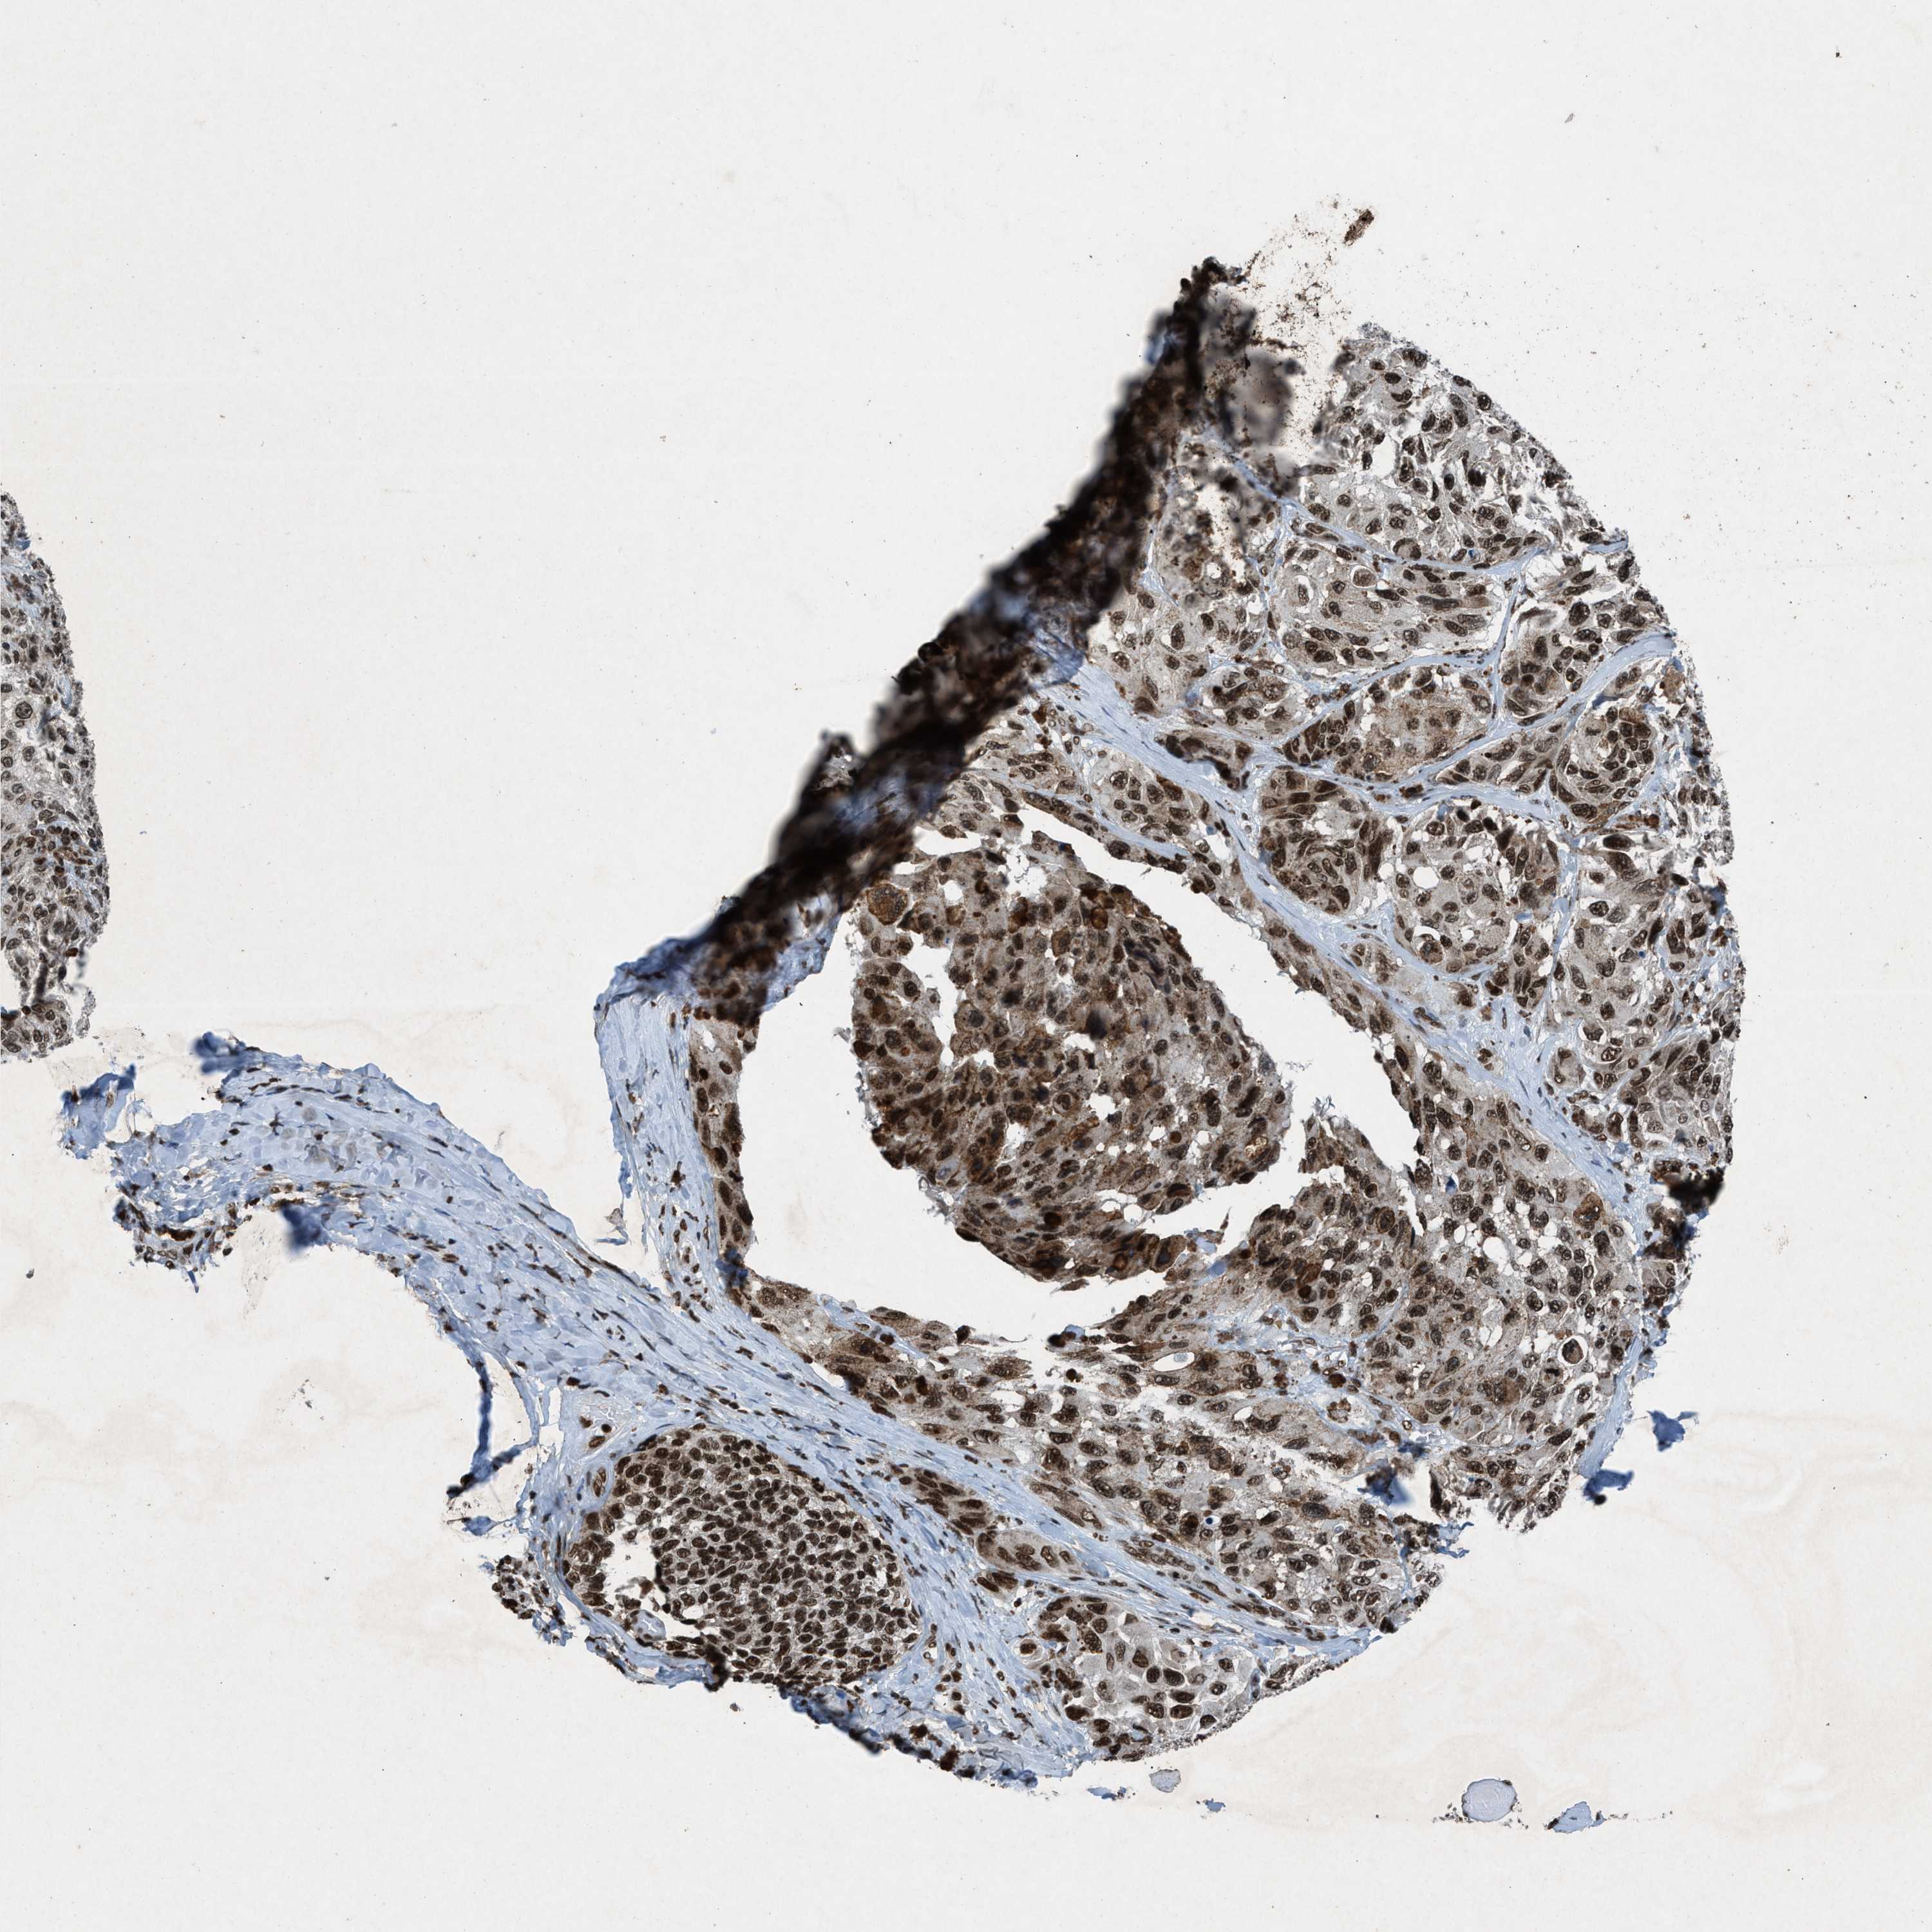

MELANOMA - Protein expressioni

A mouse-over function shows sample information and annotation data. Click on an image to view it in a full screen mode. Samples can be filtered based on level of antibody staining by selecting one or several of the following categories: high, medium, low and not detected. The assay and annotation is described here.

Note that samples used for immunohistochemistry by the Human Protein Atlas do not correspond to samples in the TCGA dataset.

Antibody stainingi

Antibody staining in the annotated cell types in the current human tissue is reported as not detected, low, medium, or high, based on conventional immunohistochemistry profiling in selected tissues. This score is based on the combination of the staining intensity and fraction of stained cells.

Each image is clickable and will lead to virtual microscopy that enables deeper exploration of all samples and also displays staining intensity scores, fraction scores and subcellular localization as well as patient and tissue information for each sample.

Antibody HPA061593

Antibody CAB016327

Staining

High

Medium

Low

Not detected

Intensity

Strong

Moderate

Weak

Negative

Quantity

>75%

75%-25%

<25%

None

Location

Nuclear

Cytoplasmic/membranous

Cytoplasmic/membranous,nuclear

Malignant melanoma, NOS

Malignant melanoma, Metastatic site